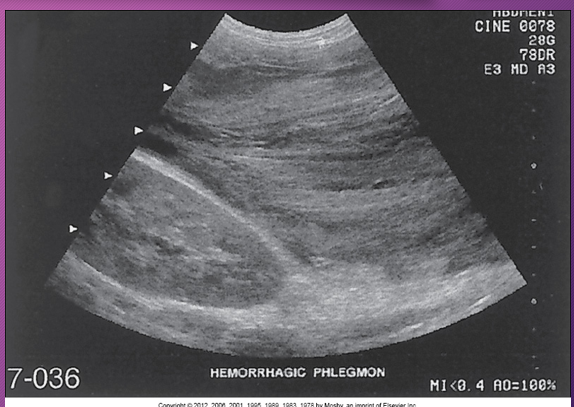

Hemorrhagic pancreatitis is a rapid progression of ______ pancreatitis with _______ of pancreatic ______ and subsequent __________

rapid; acute; rupture; vessels; hemorrhage

In _______ pancreatitis, there is diffuse _____ destruction of the pancreatic substance caused by a sudden escape of ______ pancreatic ________ into the ______ parenchyma

hemorrhagic; enzymatic; active; enzymes; glandular

Pancreatic enzymes cause focal areas of fat ______, _____ and ______ the pancreas, which leads to _____ of pancreatic ______ and _______

necrosis; in and around; rupture; vessels; hemorrhage

Patients with ______ pancreatitis has sudden _______ destruction of the pancreas AFTER an ______ binge or an excessively _____ meal

hemorrhagic; necrotizing; alcoholic; large

Sonographically, hemorrhagic pancreatitis depends on the ____ of the hemorrhage

age

Sonographically, a ______ necrosis may be seen as a ___- defined, ________ mass in the area of the pancreas

fresh; well; homogenous

Sonographically, at ____ week, the mass (hemorrhage) may appear ____ with ____ elements or _______

1; cystic; solid; septation

Sonographically, after _____ weeks, the hemorrhage may appear ______

several; cystic